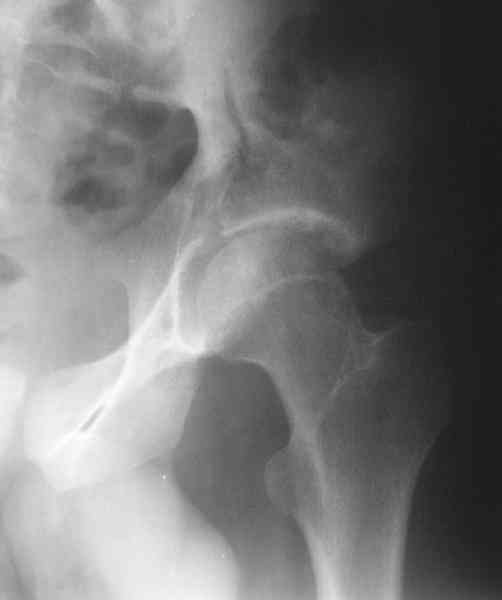

Мужчина 33 лет получил травму в шахте (придавило вагонеткой) 6 недель назад. Изолированное повреждение вертлужной впадины.

В местной больнице отлежал несколько недель на вытяжении. После выписки амбулатрный травматолог направил в институт. На сегодня, похоже, уже имеется неправиильное сращение. См. картинки.

Dear all, A male 23 y.o. injured 6 weeks ago - mine trauma, impacted by a carriage. Isolated injury of the acetabulum. At the initial hosptial was on bed traction some weeks. After discharge visited anotheк orthopaedic surgeon who referred him to our unit. To date looks like a malunion. Images attached. The question is about what to do now - either leave it as is or perform open reduction? If the latter what approach, reduction manoeuvres and fixation would you advice? Thx in advance!